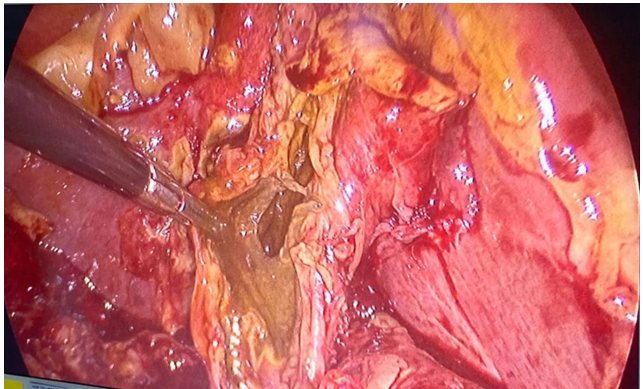

Diante do diagnóstico de colecistite aguda grave, foi indicada abordagem cirúrgica de urgência. No intraoperatório, observou-se vesícula com paredes necrosadas, intensas aderências e distorção completa da anatomia do triângulo de Calot, impossibilitando a identificação segura do pedículo biliar.

Figura 1 – Aspecto intraoperatório demonstrando vesícula biliar com paredes espessadas e necrosadas, com extravasamento de bile e importante processo inflamatório, dificultando a dissecção do triângulo de Calot.

Optou-se por estratégia bail-out com colecistectomia subtotal videolaparoscópica por via fundo-cística. O infundíbulo foi ligado com fio de nylon 0.0 e a parede posterior necrosada aderida ao fígado foi cauterizada, sendo posicionado dreno em loja vesicular.